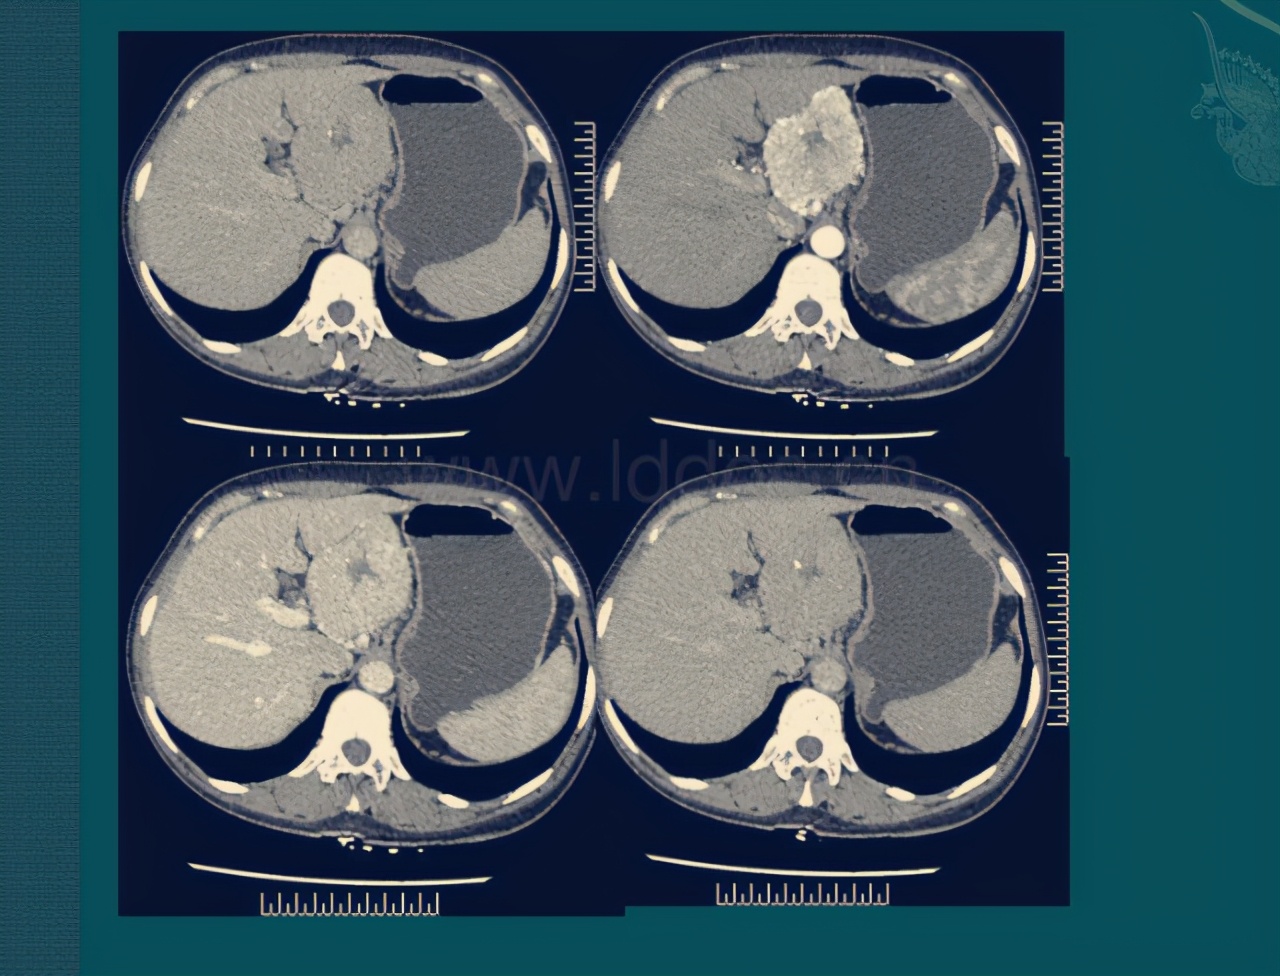

第一次化疗完我妈状态还可以,我不放心在省城治疗,就带我妈去了中国医学科学院肿瘤医院挂了个号去问诊,黄牛那买的,三百一张,医生说的治疗方案和省城的一样,所以我又带着我妈回去了,因为是一样的治疗方案,并且家中经济状况不支持在北京治疗,所以又回到我们省人民医院了,然后就开始了21天去一趟郑州的路程!化疗反应一次比一次重,慢慢地也开始掉头发,三个疗程结束后做64排增强CT,结果提示肿瘤缩小,也就是说有手术的机会了,但是医生说风险很大,我心里顿时又没谱了。

四月三号,我妈妈出院了!21天后我们又去医院做化疗了,术后五次化疗,共计八个疗程,结束后就是三个月复查一次啦,一直结果都挺好的,直到2019年年底,我妈后背开始疼痛,以为是胆囊炎,我妈的CT报告也说了,胆囊壁厚,吃了治胆囊炎的药也是微乎其微,后来就去我们县医院治疗,因为当时已经是春节后疫情期间了,医生说是肠梗阻,治疗了几天慢慢不疼了,后来就出院了,出院没几天又开始疼,期间一直在吃止疼药,也买了中药颗粒,后来我说干脆去市里吧,就这样,我们又去市人民医院治疗了,入院后重新做的一系列检查,终于找到原因了,腹膜后淋巴结,医生建议我们去做个PET CT,但是市级医院没有设备,我就带着我妈去郑州省人民医院做的检查!